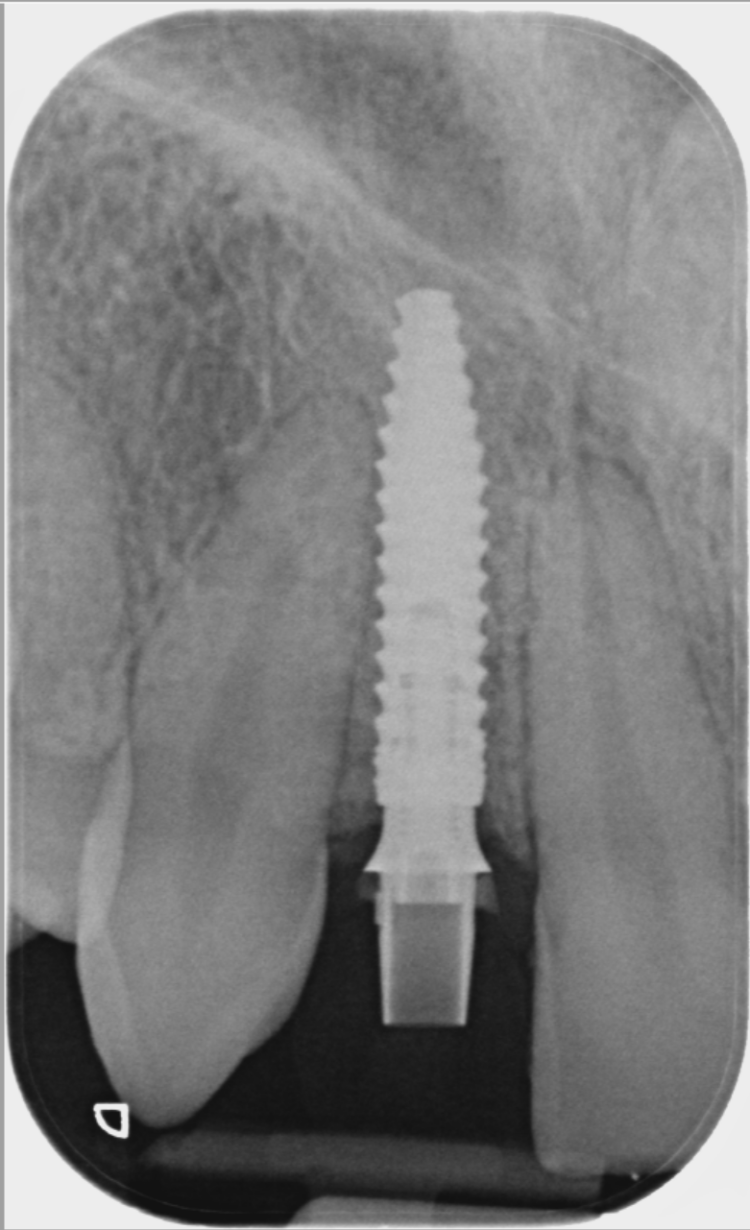

A CBCT scan was taken using a Morita X800. This dataset was imported into the planning software, where it was merged with the STLs of the anatomically correct diagnostic digital wax-up and modules.  With the anatomically correct diagnostic wax-up, there was no ambiguity regarding planning the implant position, angle and depth with precision. I like to plan these types of cases myself, but it is possible to outsource the planning stage for clinicians who are new to the process and looking to increase their workflow efficiency. For this case, I wanted to build up the gingival thickness in order to improve the papillae around the implant sites. The surgical plan, therefore, included soft tissue grafting.

On the day of surgery, a split-thickness envelope flap was raised. Two CONELOG® Progressive-Line implants were placed through the surgical guide in the pre-determined lateral incisor positions. Soft tissue augmentation was performed simultaneously with the implant placement, and the site was sutured and closed without tension. The implants were immediately loaded using provisional crowns that were pre-fabricated in the lab.

The CONELOG implants were selected because they provide a very stable connection and feature a geometry that facilitates high primary stability, which is important when placing immediate implants. They also integrate very successfully – we have had better results with these implants than with other products that are available. I also appreciate the simplicity of the keyless guided surgery kit.